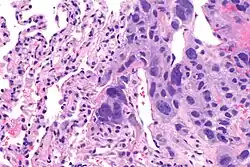

Choriocarcinomas are exceptionally rare which account for 2.1%-3.4% of all OGCTs.[10] Under gross examination, the syncytiotrophoblast cells are aligned in a plexiform arrangement with the mononucleated cytotrophoblast cells surrounding the foci of the hemorrhage.[1] Choriocarcinomas can be divided into gestational choriocarcinomas and non-gestational choriocarcinomas which have immunohistochemical differences.[11]